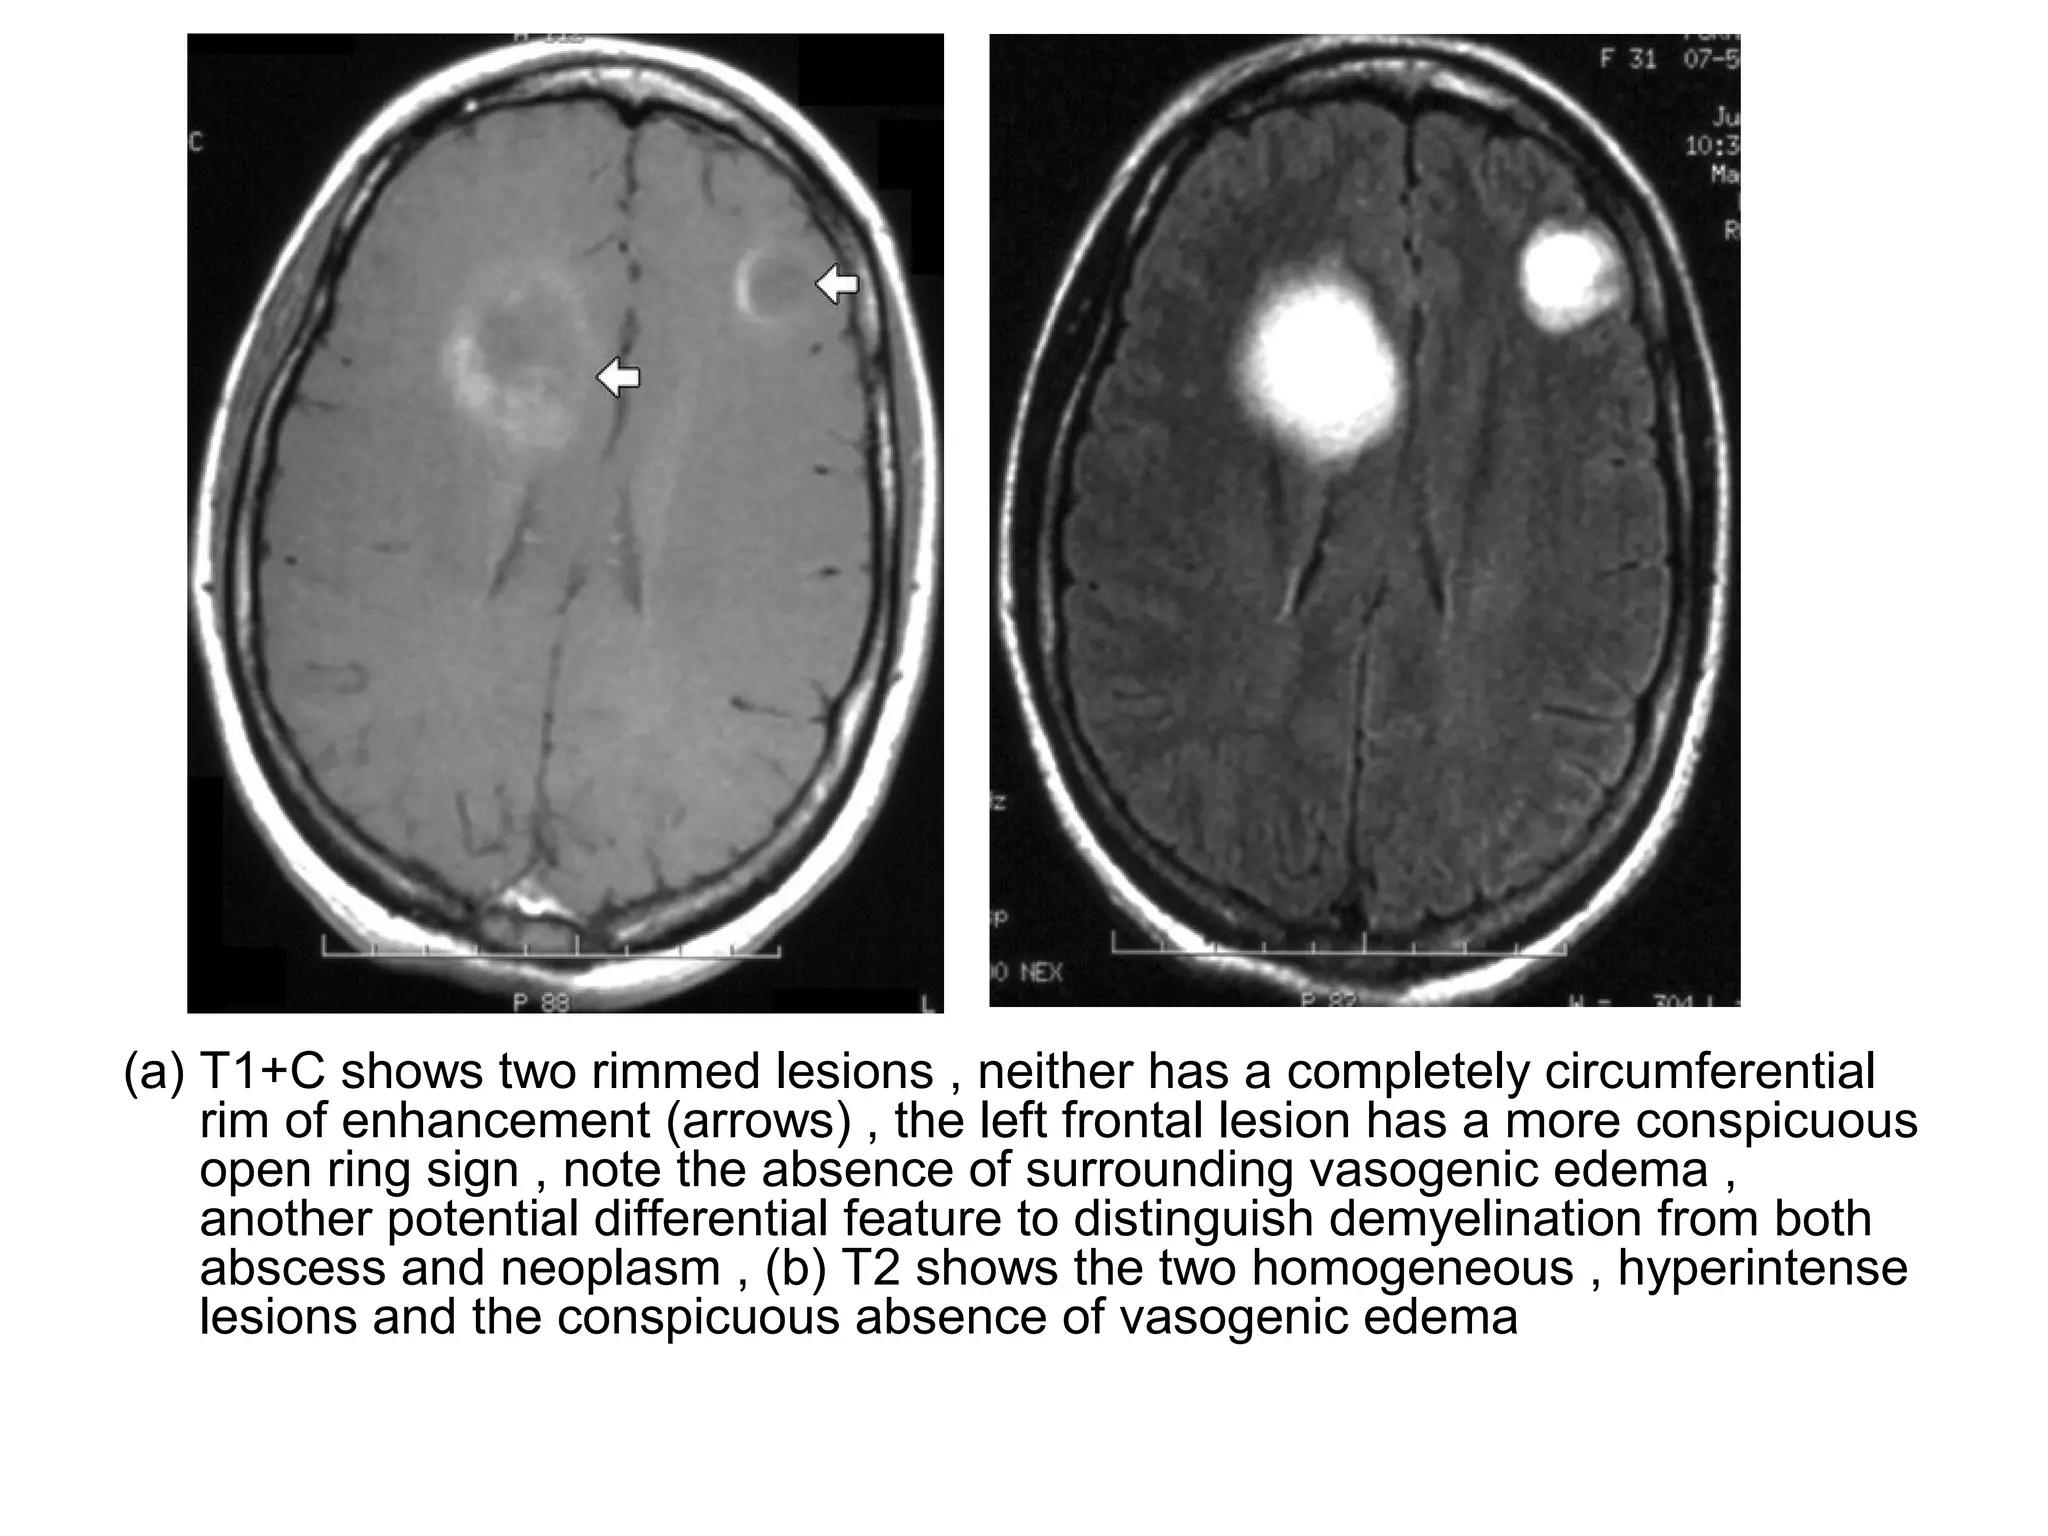

(a) T1+C shows two rimmed lesions , neither has a completely circumferential

rim of enhancement (arrows) , the left frontal lesion has a more conspicuous

open ring sign , note the absence of surrounding vasogenic edema ,

another potential differential feature to distinguish demyelination from both

abscess and neoplasm , (b) T2 shows the two homogeneous , hyperintense

lesions and the conspicuous absence of vasogenic edema